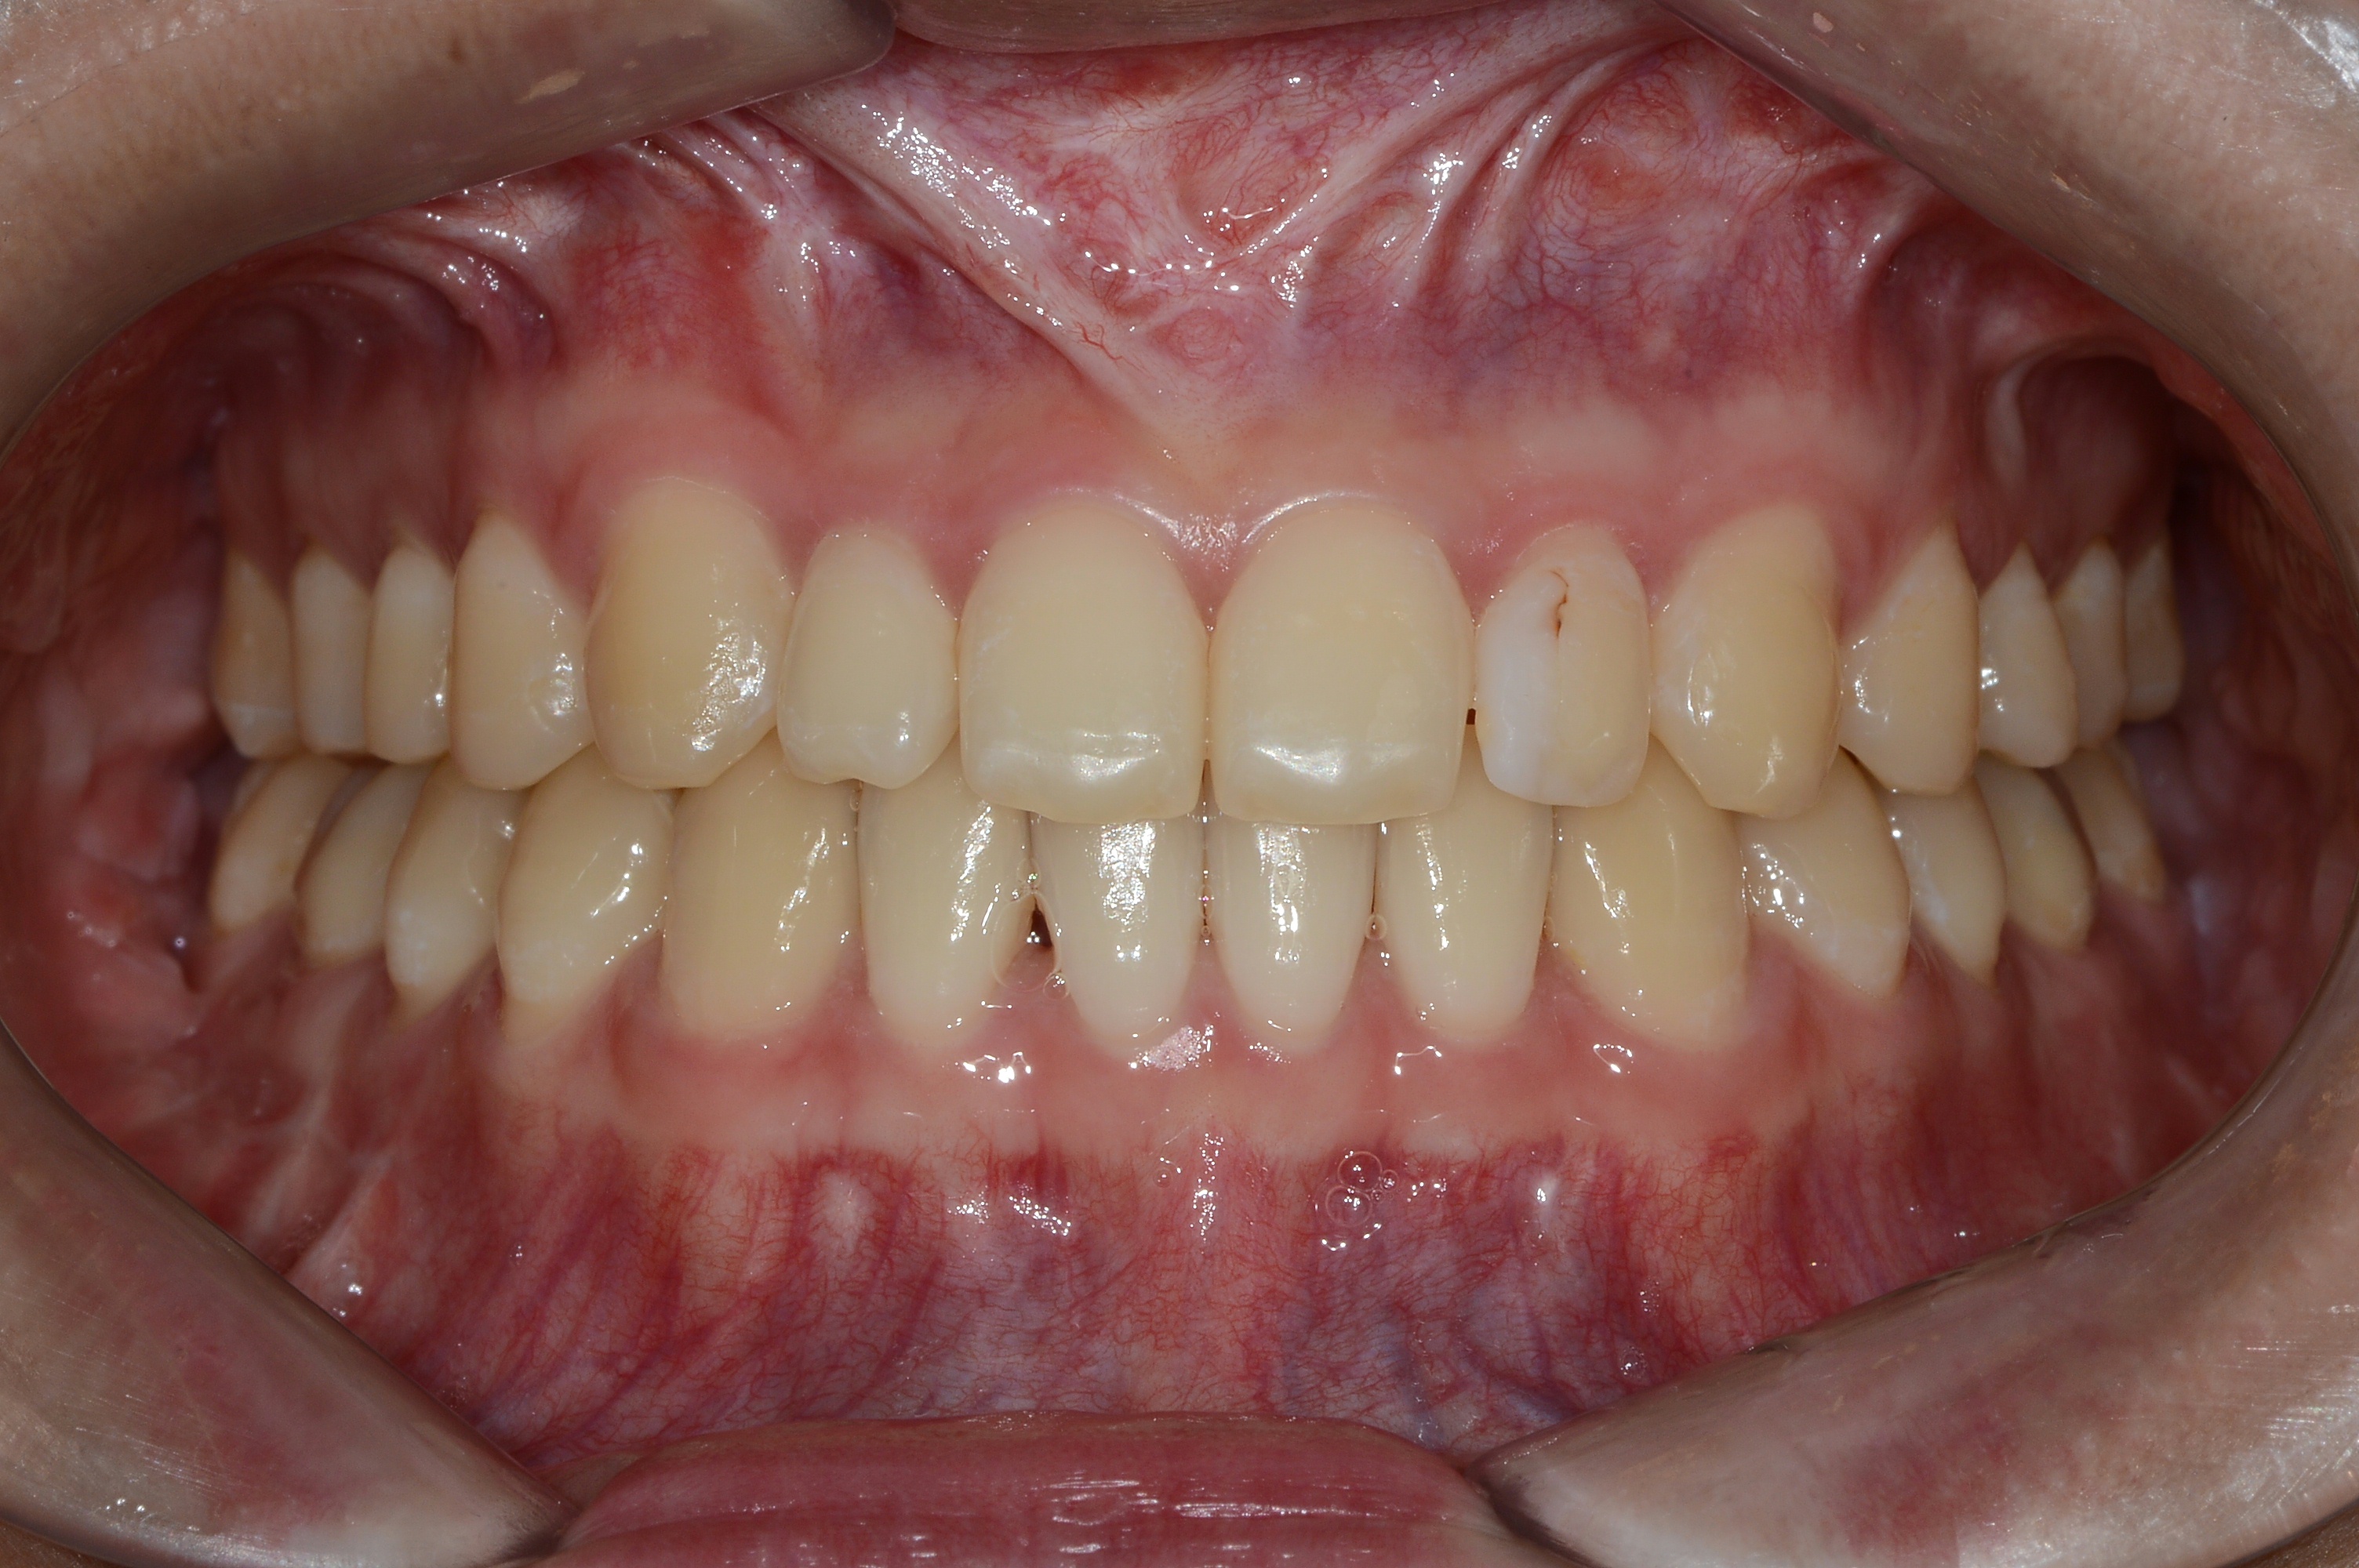

치료 후 사진입니다.